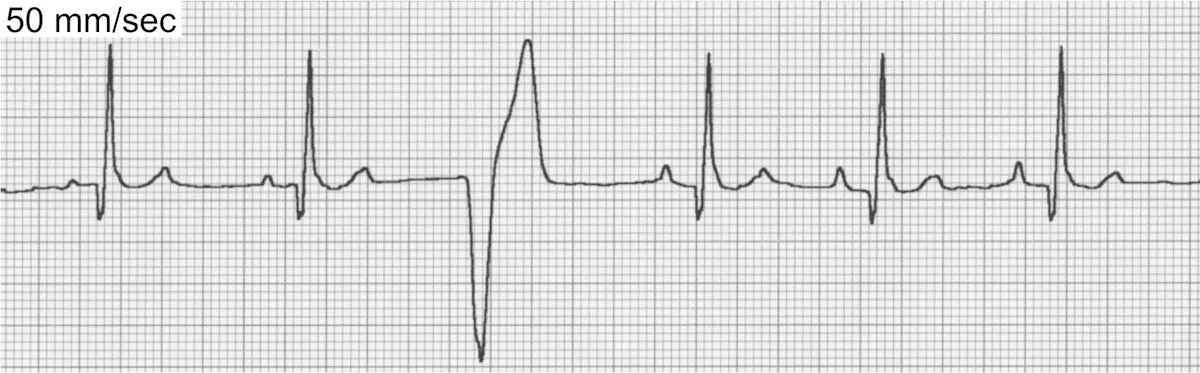

Ventricular Premature Complexes

VPCs (Figure 5) can be associated with significant inflammatory, structural, toxic, infiltrative, traumatic, or ischemic heart disease. VPCs are also common in patients with noncardiac disease (eg, gastric dilatation-volvulus [GDV], splenic disease/surgery, hyperthyroidism, sepsis, anemia, hypoxia, myocarditis/infectious disease, coagulopathies). Patients with elevated sympathetic tone from extreme excitement or pain may also display VPCs, as well as drug therapy with digoxin, anesthetics (especially short-acting thiobarbiturates), and catecholamines.

ECG of ventricular premature complexes

ECG of ventricular escape beats

VPCs generally occur <1 R-R interval from the preceding sinus beat (vs ventricular escape beats [Figure 5B] that generally occur >2 R-R intervals from the preceding sinus beat) and are not associated with preceding P waves. Care must be taken to exclude these arrhythmias from sinus rhythm with chamber enlargement patterns or sinus rhythm with conduction disturbances.

The decision to treat VPCs can be difficult. Frequent and multiform VPCs in the presence of underlying heart disease, especially with clinical signs, will necessitate treatment. Infrequent, uniform VPCs without clinical signs or heart disease uncommonly require treatment. Treatment for VPCs secondary to underlying metabolic disease is usually not indicated and therapy should instead be aimed at correcting the underlying condition.